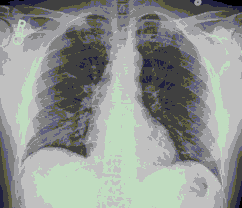

4.3. ЛУЧЕВАЯ ДИАГНОСТИКА COVID-19

Методы лучевой диагностики применяют для выявления COVID-19 пневмоний, их осложнений, дифференциальной диагностики с другими заболеваниями легких, а также для определения степени выраженности и динамики изменений, оценки эффективности проводимой терапии.

Лучевые методы также необходимы для выявления и оценки характера патологических изменений в других анатомических областях и как средства контроля для инвазивных (интервенционных) медицинских вмешательств.

К методам лучевой диагностики патологии ОГК пациентов с предполагаемой/установленной COVID-19 пневмонией относят:

- Обзорную рентгенографию легких (РГ),

- Компьютерную томографию легких (КТ),

- Ультразвуковое исследование легких и плевральных полостей (УЗИ).

Стандартная РГ имеет низкую чувствительность в выявлении начальных изменений в первые дни заболевания и не может применяться для ранней диагностики. Информативность РГ повышается с увеличением длительности течения пневмонии. Рентгенография с использованием передвижных (палатных) аппаратов является основным методом лучевой диагностики патологии ОГК в ОРИТ. Применение передвижного (палатного) аппарата оправдано и для проведения обычных РГ исследований в рентгеновском кабинете. В стационарных условиях относительным преимуществом РГ в сравнении с КТ являются большая пропускная способность. Метод позволяет уверенно выявлять тяжелые формы пневмоний и отек легких различной природы, которые требуют госпитализации, в том числе направления в ОРИТ.